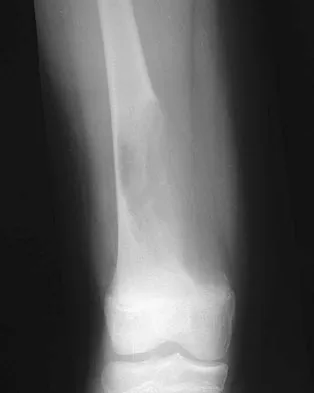

Figures 4a through 4c show the radiographs of a 43-year-old woman who sustained a twisting injury to her right ankle. She has ankle pain and tenderness medially and laterally. To help determine the optimal treatment, an external rotation stress radiograph of the ankle is obtained. This test is designed to evaluate the integrity of what structure?

Explanation

In the presence of a supination external rotation-type fracture of the distal fibula (Weber type B), stability of the ankle is best assessed by performing an external rotation stress AP view of the ankle. This test is used to assess the integrity of the deltoid ligament. The presence of a deltoid ligament rupture results in instability and generally is best managed surgically. The gravity stress test can also be used. Egol KA, Amirtharajah M, Tejwani NC, et al: Ankle stress test for predicting the need for surgical fixation of isolated fibular fractures. J Bone Joint Surg Am 2004;86:2393-2398. McConnell T, Creevy W, Tornetta P III: Stress examination of supination external rotation-type fibular fractures. J Bone Joint Surg Am 2004;86:2171-2178.